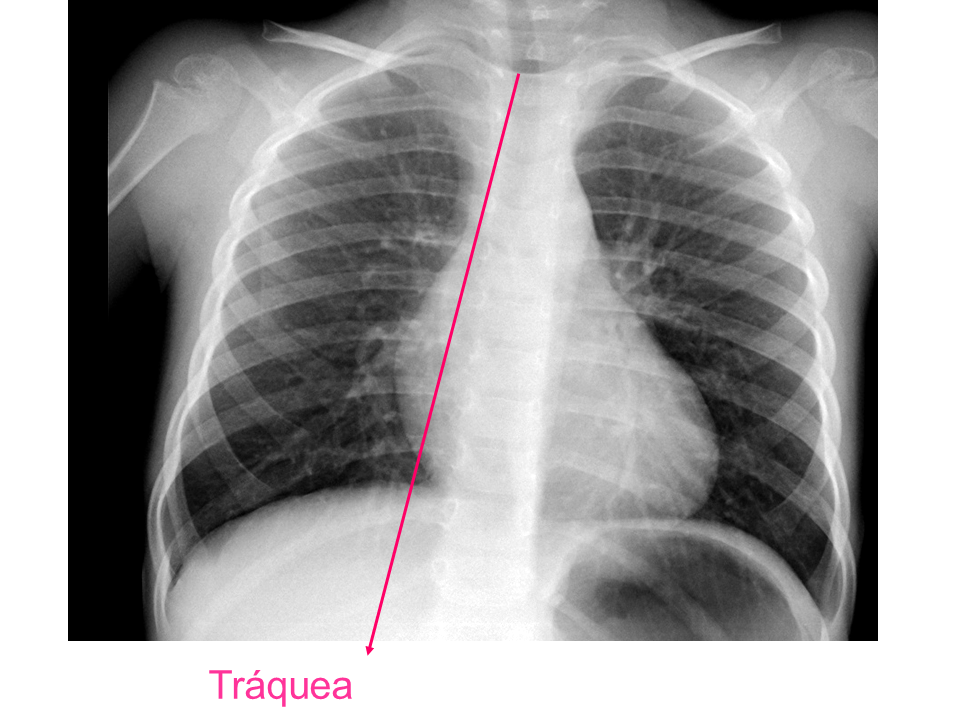

Para una adecuada lectura sistemática de la radiografía de tórax, debemos conocer la anatomía radiológica básica e identificar determinadas estructuras2.

• Tráquea